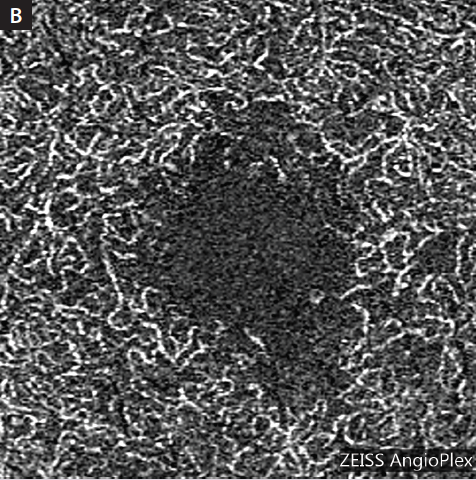

The image detail and resolution achieved with OCTA is remarkable (Figure), and there are no focusing issues as can be seen with traditional angiography. Even when compared with other systems that use scanning laser ophthalmoscopy, in which focus errors are drastically reduced, OCTA images are much more detailed and are not obscured by leakage from incompetent or damaged vessels.

Figure. Deep plexus images taken with the Cirrus HD-OCT 5000 and AngioPlex OCT Angiography platform showing the striking contrast between a normal eye (A) and an eye with early diabetic changes (B).

One unique aspect of OCTA that I did not appreciate at first was the ability to segment layers of the retina and deep vasculature. For example, one can image the deep retinal capillary plexus in isolation from the overlying superficial vessels. Using this segmentation feature, one can better identify early changes to the foveal avascular zone in patients with diabetic retinopathy and understand and visualize conditions affecting the middle retina (eg, paracentral acute middle maculopathy) more effectively.